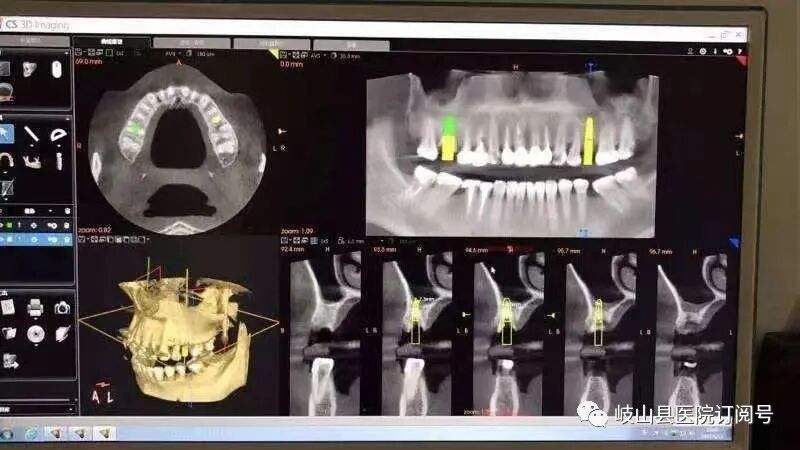

卡瓦CBCT即卡瓦口腔颌面锥形束CT(cone beam computed tomography),其基本原理是X线发生器以较低的射线量(通常球管电流在10毫安左右)围绕投照体做环形数字式投照,然后将围绕投照体多次数字投照后“交集”中所获得的数据在计算机中“重组”,进而获得高清三维图像。卡瓦X-TREND“三合一”CBCT即具有口腔曲面断层片、头颅侧位定位片和多功能CT三种拍摄功能,满足了口腔临床诊断的所有需要。

是目前国际最先进的口腔专用CT,在业界被誉为神奇的“慧眼”,具有扫描快、范围大、精度高、应用广、放射量极低的特点。可以通过其强大的处理软件功能以及面部匹配技术迅速形成清晰逼真的三维图像,较传统CT对于牙齿及颌骨组织的结构成像质量更好,彻底解决了口内牙片机、口腔全景机等口腔X射线设备影像重叠、畸变的问题,可以便捷直观地发现多种牙齿隐患问题,为口腔医生提供了精准的诊断与治疗依据。

卡瓦CBCT广泛应用于口腔各个领域:口腔颌面外科方面用于肿瘤、囊肿的范围及与上颌窦及下颌神经管的关系,颌骨骨髓炎的诊断,骨折的诊断及术前指导,阻生智齿的诊断及拔除指导,多生牙及埋伏牙的定位及毗邻关系,颞下颌关节病的诊断等;牙体牙髓方面可以清晰观察根管的数目及形态、能够发现变异的细小根管、早期的根尖炎症、牙根折裂等情况;牙周病方面可以确定牙周病的病变程度及指导治疗;牙列错颌畸形矫治方面用于研究颅面生长发育,诊断分析、矫治设计、前后对比,头影测量等;口腔种植方面涵盖了种植牙的每一个种植细节,提供了可靠的理论依据,确保种植牙手术的成功率。(口腔科  陈亚萍)